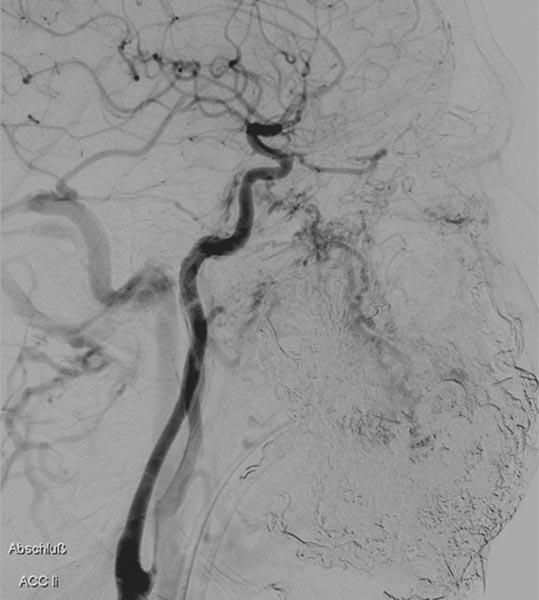

In der Spätphase der DSA (laterale Ansicht) über die linke A. carotis interna. Nach erfolgreicher mehrfacher Embolisation ist auch die Versorgung des Nidus der AVM über diese kritischen Äste verschlossen und die A. ophtalmica erhalten.